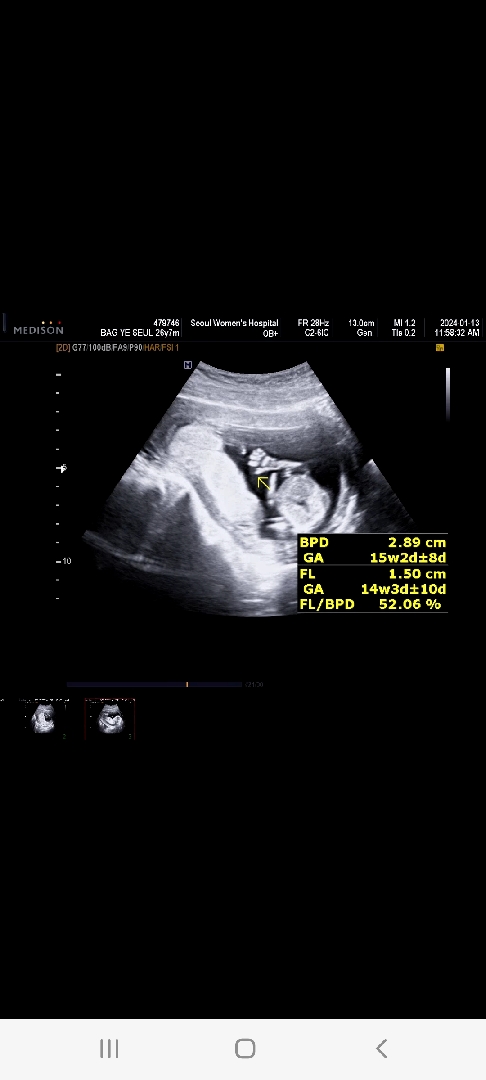

14주차♡

선생님이 14주차2일에 보기힘들다는데 지난번 12주차에도 초음파를보니 저렇게 손가락을쫙피고 확인시켜주더라구용ㅎ마치 엄마아빠가보는걸 아는거라는듯이 갈때마다 잘움직이고 하루하루너무 신기하고 뿌듯하네용ㅎㅎ 다른어머니들도 같은마음이신가용ㅜㅜㅎㅎ